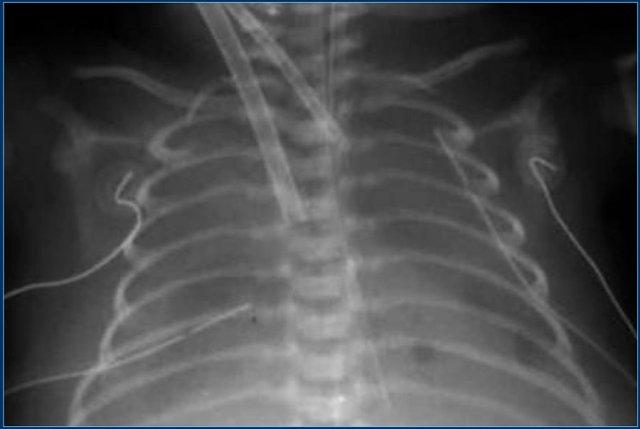

Đường truyền tĩnh mạch rốn (6)

Quan sát hình ảnh.

Sau đó tiếp tục đọc.

Các phát hiện bao gồm:

- Đường truyền tĩnh mạch rốn quá sâu, đầu catheter đang nằm trong nhĩ phải.

- Đường truyền động mạch rốn ở mức T10 (vị trí lý tưởng là từ T6 đến T9).

- Ống nội khí quản được đặt quá sâu.

Đầu ống cần nằm cách chỗ phân đôi khí quản 1 cm về phía trên.